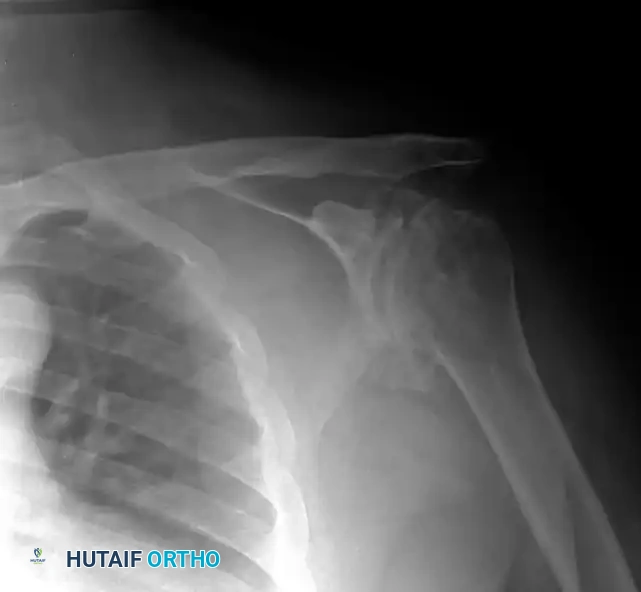

Preoperative Imaging:

Standard radiographs must include a true anteroposterior (Grashey), axillary lateral, and scapular Y view. A non-contrast CT scan is mandatory for evaluating glenoid bone stock, version, and morphology (utilizing the Walch classification for posterior wear).